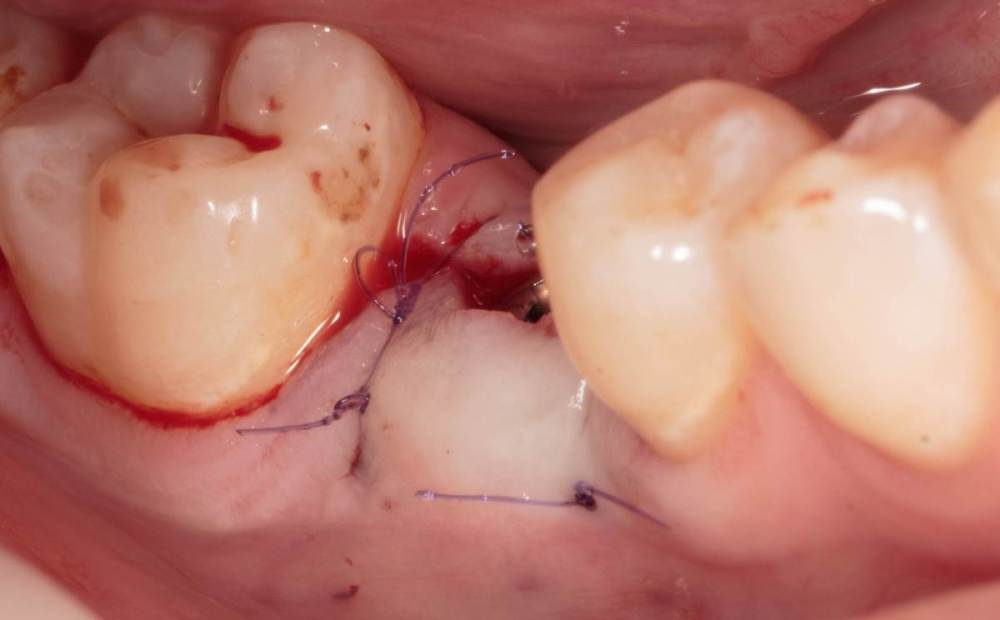

Женька Опубликовано 19 августа, 2023 Поделиться Опубликовано 19 августа, 2023 ?️. Поймал себя на мысли, что испытываю проблемы с ушиванием+ССТ на формике. А именно-не устраивает результат "прирощённой" десны. Вроде на ушивании есть + к объёму, а на протезировании "яма" вестибулярно лишь немного уменьшилась. Подскажите, как лоскут формировать так, чтобы в слоёном пироге имплантат-формик-сст оставался объём слизистой, а не таял. Подумал, что может стоит при имплантации сразу формировать асл. А в кейсе я снова "согрешил" и поставил ультра-низкий формик. В этот раз без всяких послаблений лоскута и натяжения, кмк. Ссылка на комментарий

Борис80 Опубликовано 31 августа, 2023 Поделиться Опубликовано 31 августа, 2023 (изменено) Евгений, а если попробовать и подсыпать и подсадить? Просто объема не хватает, трансплантат меньше требуемого Изменено 31 августа, 2023 пользователем Борис80 Ссылка на комментарий